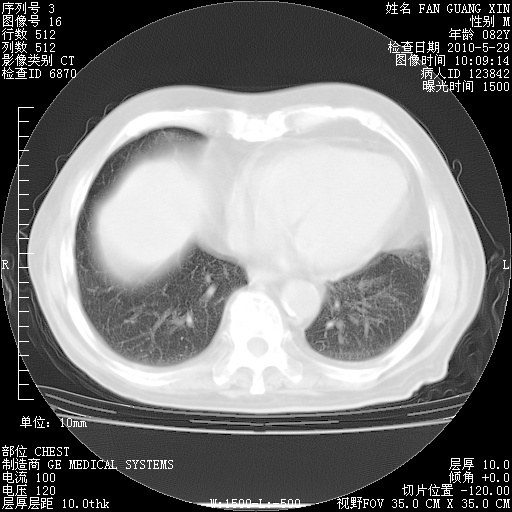

再治疗10天后的肺部CT

阅读此次胸部CT,肺间质渗出性改变较入院时有吸收。目前从体温、白细胞、中性分叶明显增高,肯定存在细菌感染(发生医院感染哦,若无消化道及泌尿系统等感染的依据,肺部感染可能大)。若你院头孢哌酮舒巴坦钠耐药率较高,同意你的方案,若48小时体温仍高,可考虑使用碳青霉稀类抗菌药物,同时可予超声雾化、注意滴数时加大液体量。白蛋白33.30g/L较低哦,需加强营养等支持治疗。